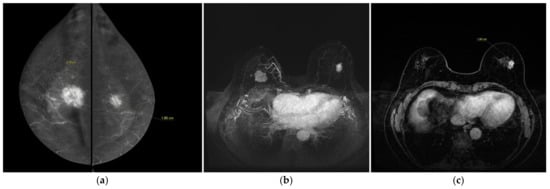

Both CESM and BMR correctly identify a contralateral breast cancer (an invasive ductal carcinoma, no specific type) (Figure 2).

Figure 2.

A 74-year-old women with synchronous bilateral breast cancer. Patient performs mammography and ultrasound examinations because a palpable mass in the upper quadrant of the right breast. (a) CESM CC views show an irregular-enhanced mass in the right breast and an irregular-enhanced mass in the left breast. They were an invasive ductal carcinoma in the right breast (27 mm in size) and an invasive lobular carcinoma in the left (18 mm in size). (b) BMR, axial MIP (Maximum intensity projection) reconstruction shows bilateral breast cancer. Note the similarities with the CESM images (morphology of the masses and increased local vascularity in the right breast). (c) BMR, first post-contrast axial T1-weighted fat saturation dynamic axial sequence (Vibrant). Measurements of the lesions show good agreement with CESM (16 mm).

BMR showed a case of false positive contralateral enhancement.

Lesion sizes determined with CESM and breast MRI were similar (Figure 2), but were larger than those from histopathological examination.